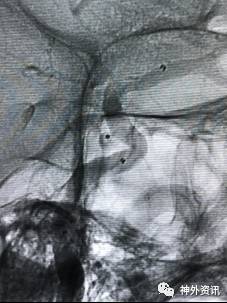

病例一

眼动脉动脉瘤,支架完全释放后,微导管成袢逆行到位

病例二

眼动脉动脉瘤,支架释放前,微导管成袢逆行到位

病例三

A1起始段动脉瘤,微导管成袢逆行到位

病例四

海绵窦区硬脑膜动静脉瘘,海绵窦下外侧干超选栓塞